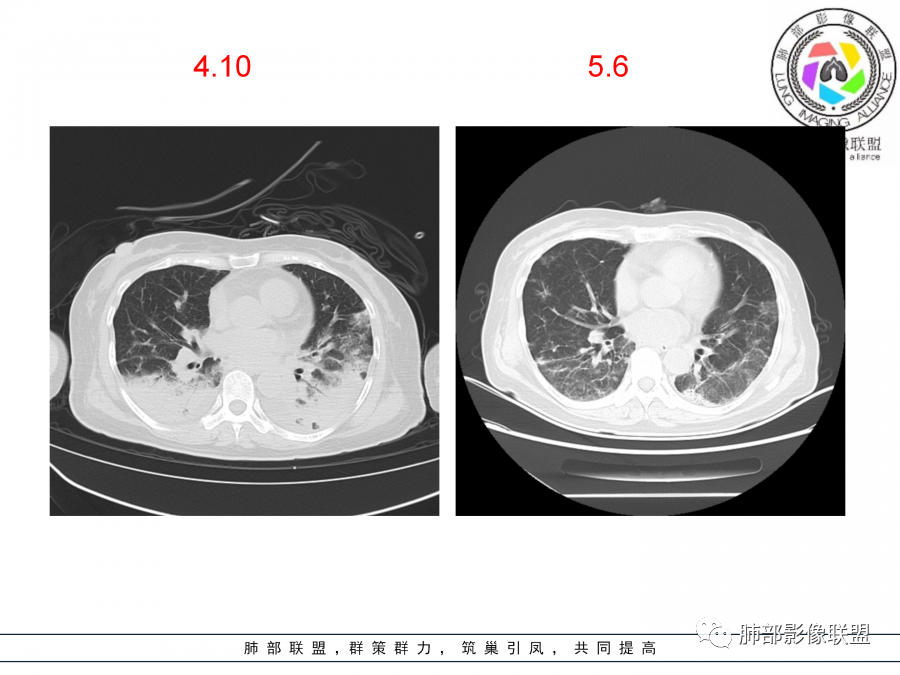

抗细菌感染无效,急性起病,影像有些机化的表现,也并非完全是机化,同时存在其他的病理进程,后期可能存在肺损伤。CTD_ILD首先考虑,sle还是干燥没法区别,干燥的概率稍大,反正都一样激素用上去再说,具体是啥进一步检查了。其他病毒感染或者特殊感染不完全排除。下一步查结缔组织病全套,唇腺活检等。大剂量激素冲击,若激素效果不好,进一步查病原学,灌洗液ngs等

还是首先考虑是ctd ild吧

干燥发病率比SLE高很多。

我遇到过两三个初诊表现为机化性肺炎的干燥。

结缔组织病也可以先表现为肺部病变,没有其他症状。